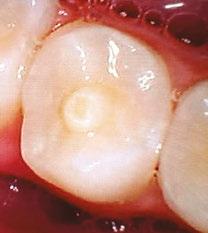

A 10-year-old female patient with a history of swelling and pain associated with tooth No. 20 was referred to our office. The patient exhibited severe dental anxiety. Upon clinical evaluation, a dens evaginatus was noted on the occlusal surface of the tooth (Figure 1). The tooth was sensitive to percussion, palpation, and bite stick while cold testing yielded no response. A periapical radiograph and CBCT scan (Carestream 9600) revealed a wide open apex and evidence of apical periodontitis, leading to the

Figure 1 (left): Dens evaginatus noted on the occlusal surface. Figure 2 (right): Preoperative periapical radiograph of tooth No. 20 showing evidence of apical periodontitis and a wide open apex

diagnosis of a necrotic pulp and symptomatic apical periodontitis of tooth No. 20 (Figures 2 and 3).